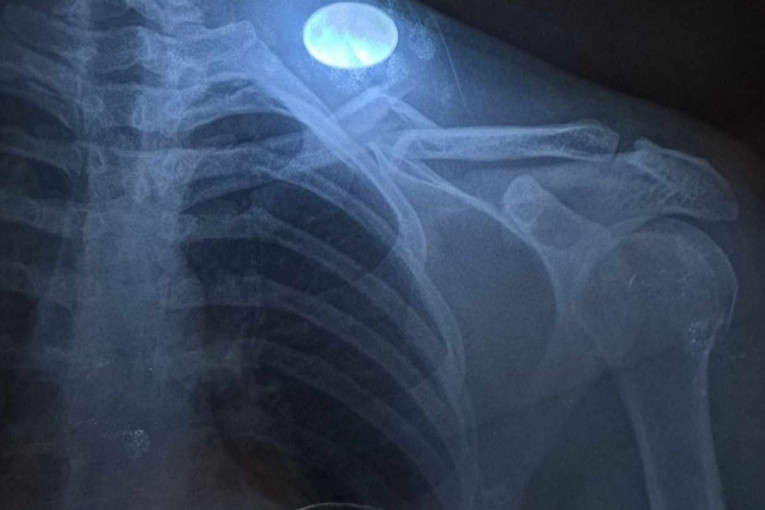

Međutim, kompletna utakmica ostala je u senci teške povrede gostujućeg fudbalera Petra Markovića koji je u 27. minutu morao da napusti igru, a dan kasnije njegov klub javnosti se obratio saopštenjem u kojem je javnost obavestio o stepenu povrede dvadesettrogodišnjeg fudbalera:

- Nakon detaljnih analiza i jutrošnjih pregleda, ponovljenog snimanja, naš prvotimac, Petar Marković pretrpeo je prelom ključne kosti na čak šest mesta. Odlukom uprave i predsednika kluba odlučeno je da se o jučerasnjim dešavanjima podnese kompletan izveštaj izvršnoj disciplinskoj komisiji.